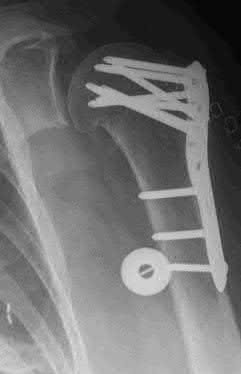

A 44-year-old male is struck by a vehicle while riding his bike. In the trauma bay, he complains of right shoulder pain . Upper extremity physical exam reveals no neurologic deficits, and an initial radiograph of the shoulder is shown in Figure A. A CT scan of the shoulder shows 1cm of posterior displacement of the tuberosity fragment. Which of the following is true regarding this injury?

The radiograph in Figure A demonstrates a posteriorly displaced greater tuberosity fracture. These injuries are often associated with anterior shoulder dislocations, and concomitant rotator cuff tears. The subscapularis attaches to the lesser tuberosity, and is not a deforming force. Open reduction and internal fixation (ORIF) is usually the treatment of choice, and it is well accepted that more than 5mm of displacement is an indication for surgery in patients that require overhead function of the arm.

Flatow et al evaluated 12 patients who were an average of five years status post ORIF of displaced greater tuberosity fractures. All fractures healed without postoperative displacement. Six patients had an excellent result and six had a good result.

Platzer et al retrospectively analyzed functional and radiographic results of 52 patients with operative treatment of displaced greater tuberosity fractures at an average time of 5.5 years from surgery compared to 9 patients with equivalent injuries treated non-operatively. Evaluation of the results of the surgical study group and the nonoperative control group, patients with reduction and fixat ion of greater tuberosity fractures had significantly better

results on shoulder function than did those with conservative treatment.